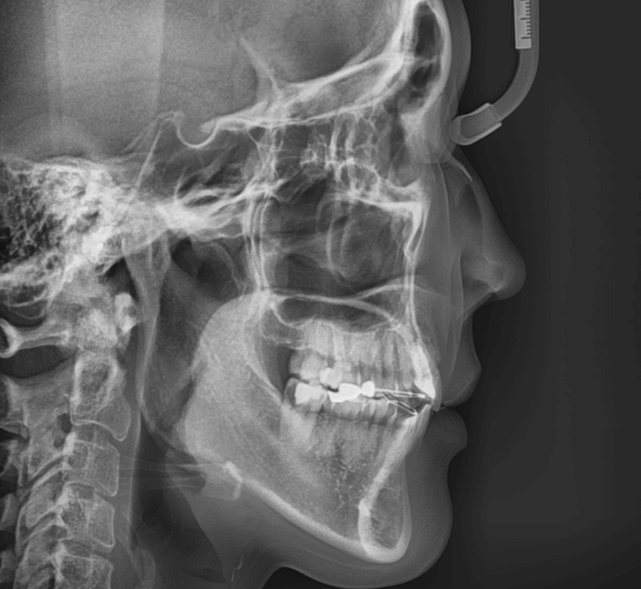

| 年齢・性別 | 15歳の女性 |

|---|---|

| 主訴 | 咬み合わせが逆であること(反対咬合)を気にされて来院された15歳7か月の女性。見た目や機能面の改善を希望されていました。 |

| 治療期間・回数 | 4年4ヶ月・28回 |

| 費用 | 900,000円 |